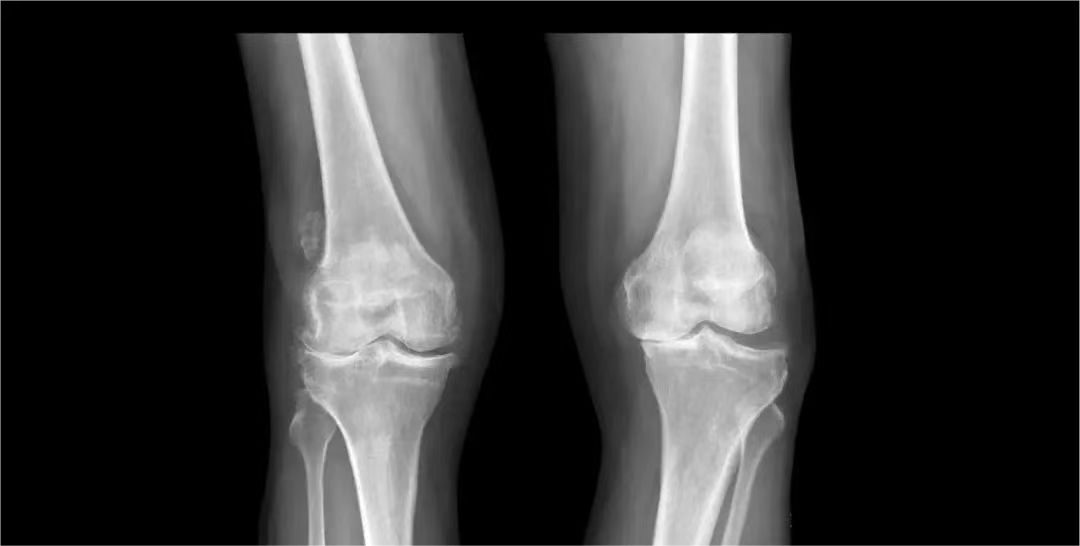

患者 女 72岁 “左侧臀部疼痛、双侧膝关节疼痛1周”

临床诊断:左侧臀大肌损伤,双侧膝关节退行性关节炎

治疗方案:冲击波疗法+漫游交互刺激技术